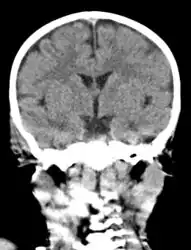

Acute mastoiditis

CT scan: Otitis media (simple arrow) and mastoiditis (double arrow) of the right side (left side in image). The external auditory canal is partially occupied by suppuration (triple arrow). 44-year-old woman